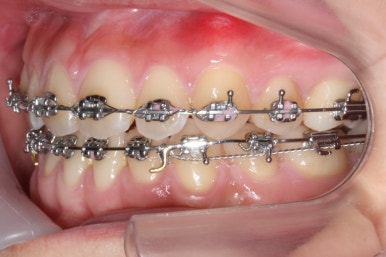

교정치료를 시작한지 3개월 밖에 지나지 않았을 시점인데도 벌써 덧니가 많이 가지런해졌습니다. 치아는 자리만 확보되면 쉽게 가지런해질 수 있습니다.

가지런해지지 않았던 아래 앞니 하나도 금새 가지런해졌습니다.

이제 가지런하게 하는 작업은 거의 종료되었고, 향후의 과정은 남은 이 뽑은 자리를 당겨주어 틈을 없애주면서도 입도 뒤로 좀 넣어주는 것이 되겠습니다.

위아래 아주 단단한 철사로 지탱해주면서 (앞니쪽에 고리가 달린 철사) 앞-뒤 치아를 서로 당겨주면서 이 뽑은 자리를 서서히 없애줍니다.